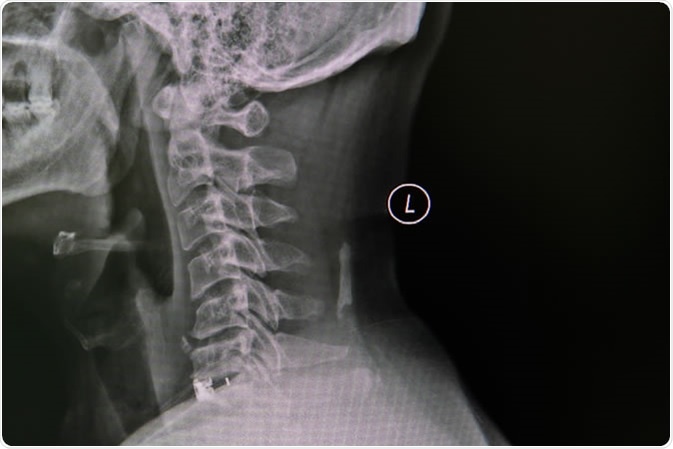

Cervical Spine, spinal cord and spondylosis, impressions with narrowing of the C5 / 6 area - Image Credit: nuiza11 / Shutterstock